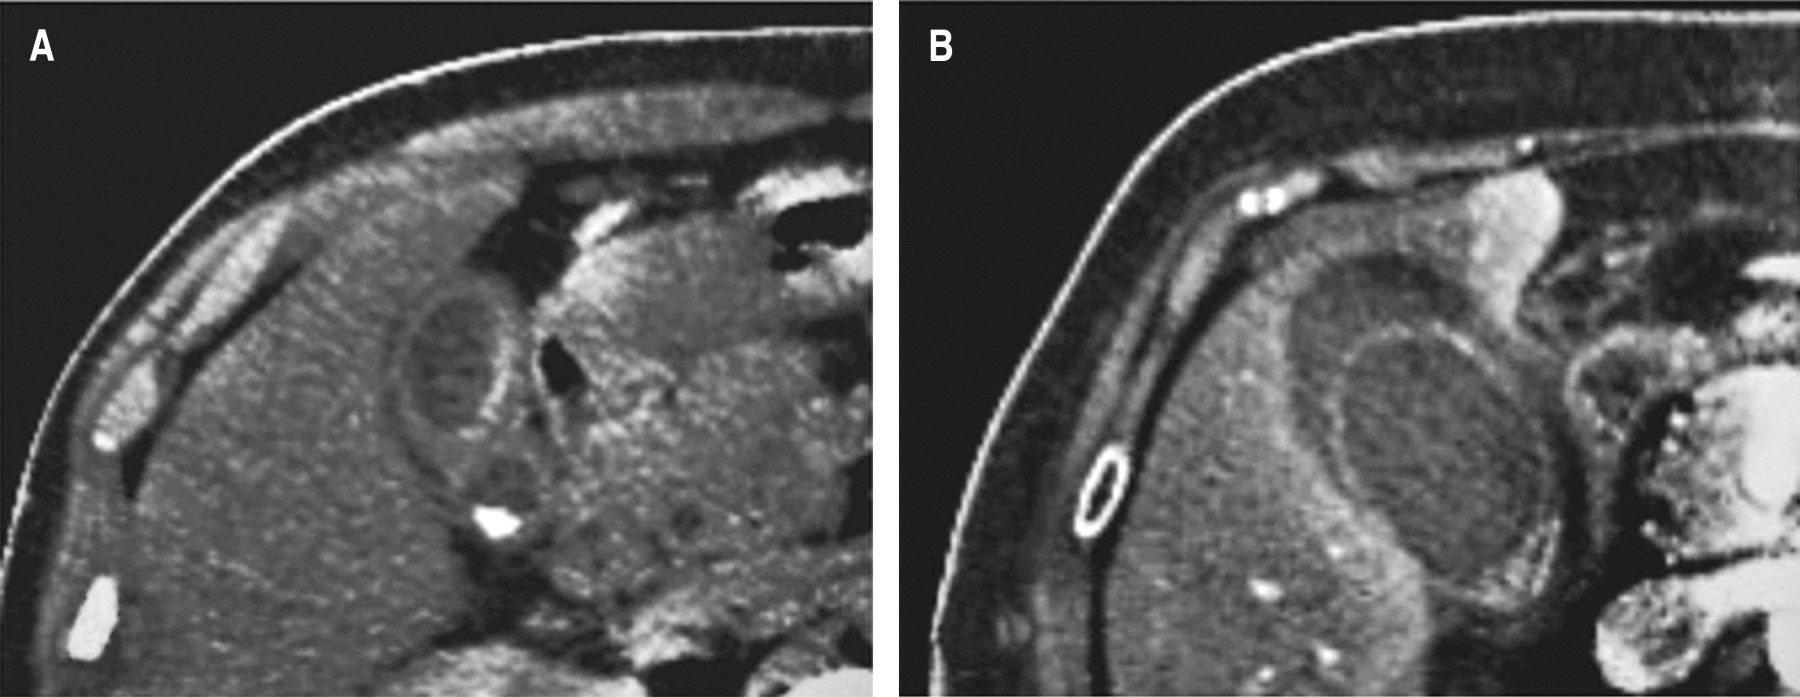

Upon admission, all patients underwent imaging studies for suspected acute cholecystitis (abdominal ultrasonography and/or abdominal tomography). In all patients, the gallbladder wall thickening of more than 5 mm (mean 8.96 mm, range 5-16 mm) was corroborated, and signs of acute cholecystitis (criteria TG-18) or structural alterations were ruled out. Differences between acute cholecystitis and gallbladder edema in the abdominal ultrasound are shown in Figure 1, and differences in the CT scan are shown in Figure 2, respectively.

Figure 1